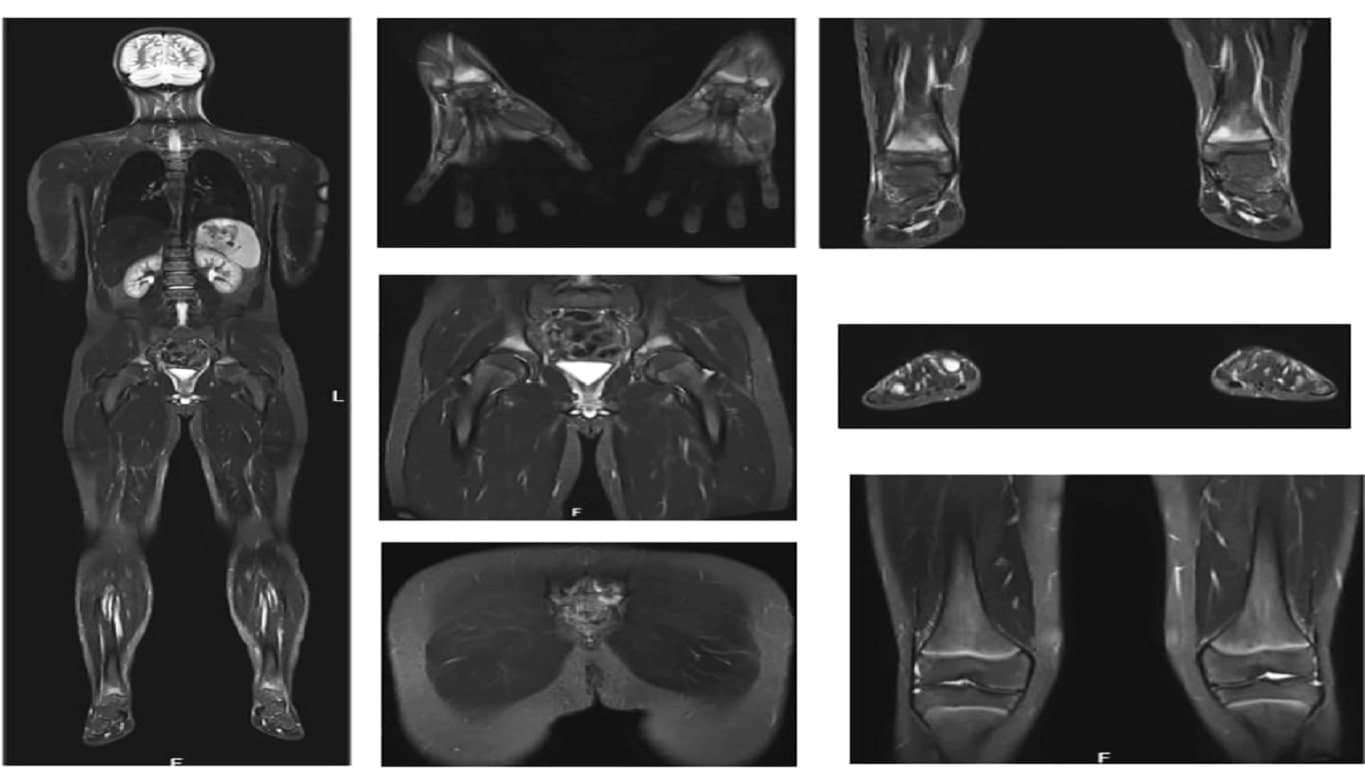

Currently, doctors and radiologists face significant challenges in the diagnostic process due to the time-consuming tasks of comparing medical images, detecting tumors, and monitoring disease progression without available software assistance. This situation is exacerbated by the increasing volume of medical imaging data, demanding faster and more accurate diagnoses. VIDA Medicals addresses this issue by offering software and AI solutions that aid in cancer detection, tumor segmentation, calcification identification, and provide options for monitoring disease progression and comparing medical images. This technology aims to alleviate the pressure on healthcare professionals, improve patient outcomes, and enhance overall healthcare efficiency.

At VIDA Medicals, we lead the charge in applying cutting-edge AI technology to transform cancer detection and prediction from medical imaging data. Our dynamic team of experts continually refines algorithms, ensuring unmatched accuracy. By harnessing AI, we equip healthcare professionals with tools for early, precise identification of cancer, enhancing clinical decision-making and patient outcomes.

Precision and reliability are paramount at VIDA Medicals. Our AI solutions are rigorously trained on diverse datasets, excelling across medical imaging modalities. The technology's ability to discern subtle anomalies allows for early cancer detection, setting a new standard in diagnostics. Through meticulous validation and continuous refinement, we provide healthcare providers with a trustworthy ally in the fight against cancer.